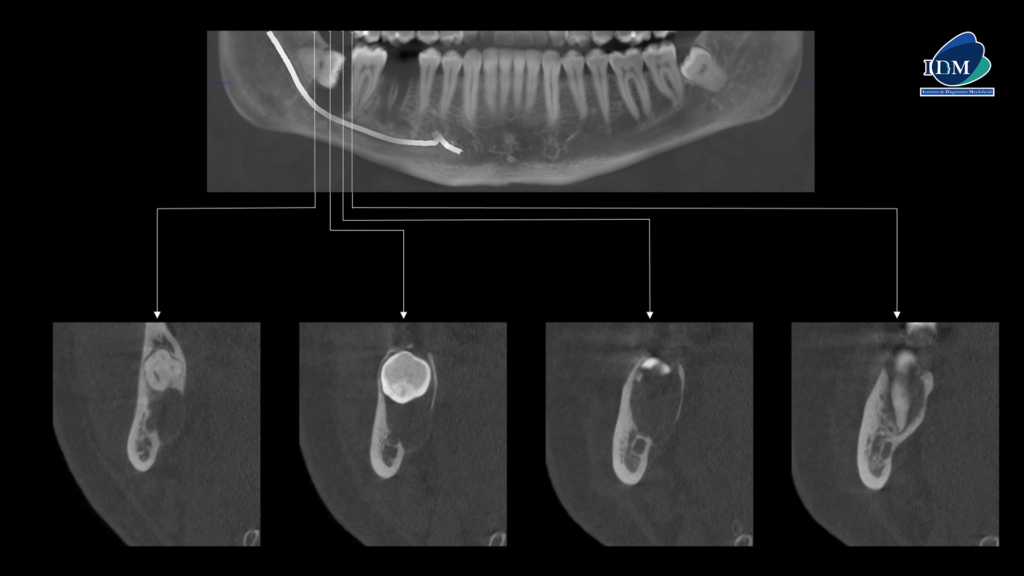

A la evaluación de la tomografía volumétrica (CBCT) en los cortes axiales (Figura 2) y transaxiales (Figura 3), se aprecia imagen isodensa pericoronaria, de limites definidos, bordes parcialmente corticalizados, que se extiende en sentido cefálico caudal desde cima del reborde alveolar hasta a nivel de cortical inferior del conducto dentario inferior, en sentido mesio distal desde distal de pieza 47 hasta tercio cervical radicular de pieza 48, que ocasiona el borramiento parcial de la lámina dura en raíz distal de pieza 47, adelgazamiento y expansión de la tabla ósea lingual, erosión parcial de la cortical de cima del reborde alveolar, borramiento parcial de la cortical del conducto dentario inferior.

CORTES TRANSAXIALES